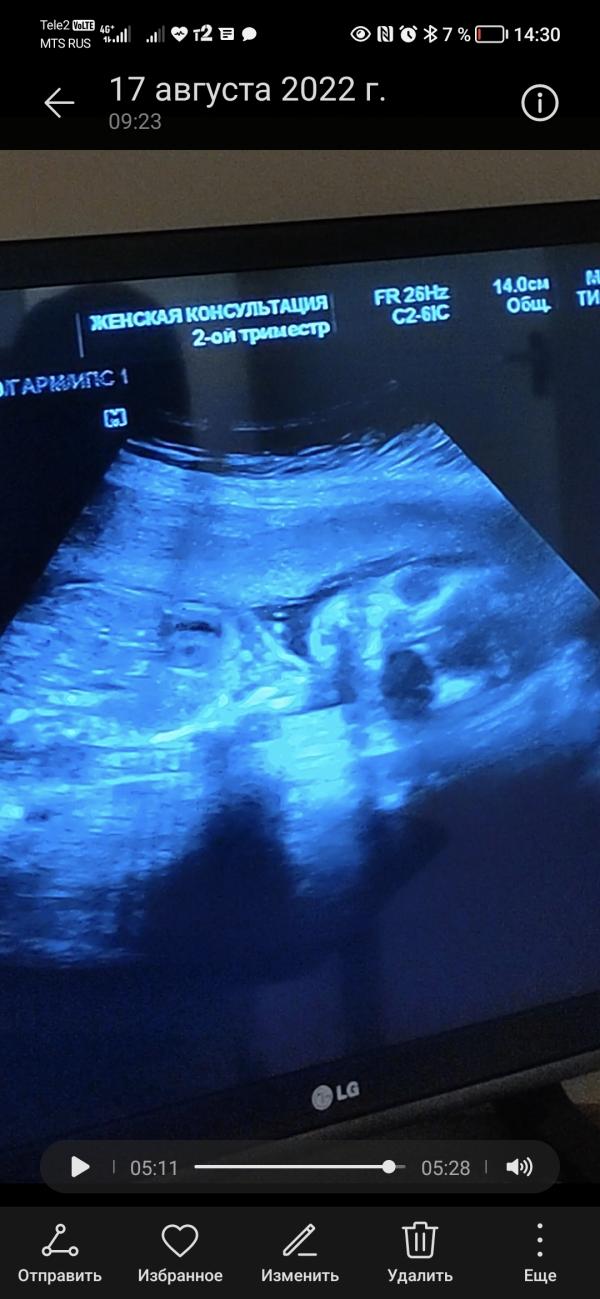

Мой малыш в 20 недель. Второй скрининг , увидели миому матки , в 16 недель не было. Врачи молчат как партизаны. Девочки не к кого не было такого